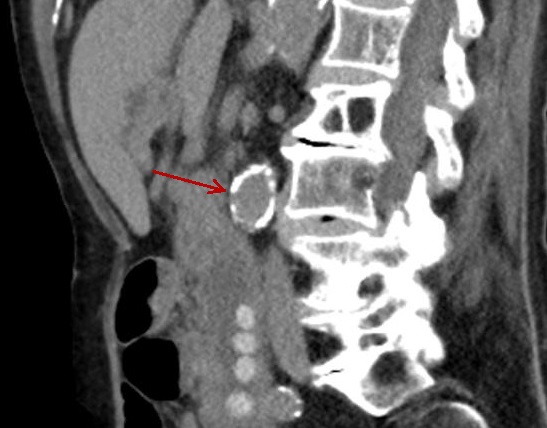

|

Image radiologique en TDM

d'une autre grand calcul choledocien .

Aspect arrondie iso-attenuance d'une calcul

choledoccienne avec contour tres hyperdensite

( Rim sign ), fleche rouge . Image TDM en

coupe sagital |